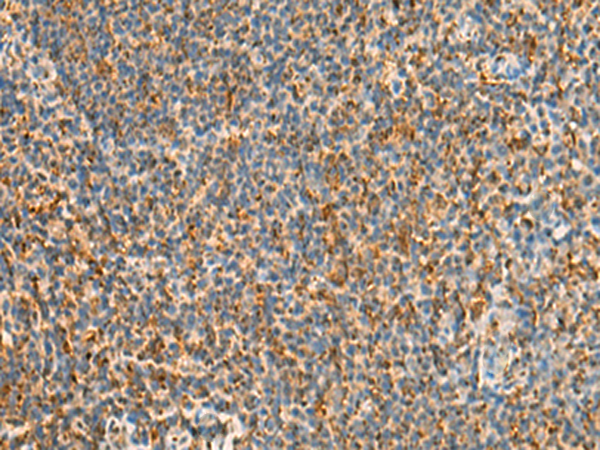

分类: 科研抗体货号: P09880别名: PDIR应用: WB,IHC反应种属: Human, Mouse, Rat

分类: 科研抗体货号: P09886别名: CHED; CHED1; CHED2; PPCD1; ZNF339; EUROIMAGE566589应用: WB,IHC反应种属: Human, Mouse

分类: 科研抗体货号: P09879别名: IDDM1; CELIAC1; HLA-DQB应用: IHC反应种属: Human

分类: 科研抗体货号: P09884别名: DR4; DRB4; HLA-DR4B应用: WB,IHC反应种属: Human

分类: 科研抗体货号: P09883别名: SS1; DRB1; HLA-DRB; HLA-DR1B应用: WB,IHC反应种属: Human